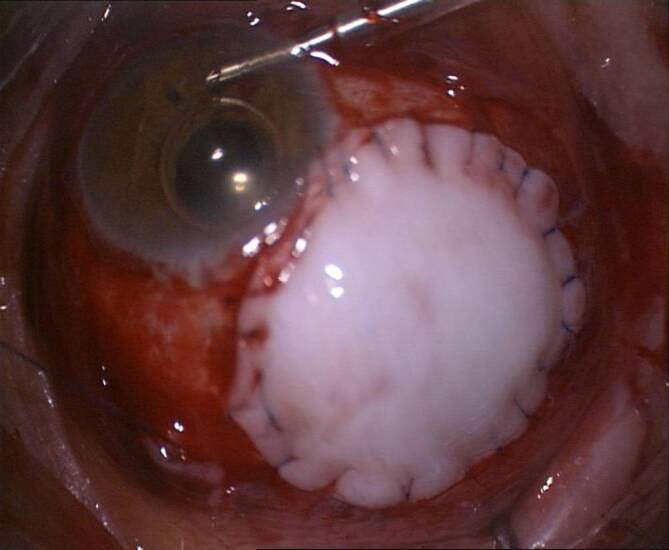

Die direkte Zyklopexie

direkte Zyklopexie

nach Naumann gilt noch immer bei geschlossenem Bulbus als Methode der Wahl [8, 13, 23, 29, 30], um bei hypotonem Bulbus, den abgerissenen Ziliarkörper an der Sklera zu refixieren. Hierfür ist eine genaue Lokalisation des Zyklodialysespaltes erforderlich. Es lohnt sich, bei Operationsbeginn zu gonioskopieren. Gelingt dies nicht, kann zuvor über eine Parazentese die Vorderkammer mit BSS gestellt werden. Dann wird auf der Sklera bzw. der Hornhaut die Ausdehnung der Zyklodialyse markiert. Alternativ lohnt sich kurz präoperativ im Liegen eine UBM-Untersuchung mit Markierung des Zyklodialysespaltes, da das Auge auch im Liegen zyklorotieren kann [39]. Nach der Peritomie wird ein Skleradeckel über dem Zyklodialysespalt von ca. 50 % Skleratiefe limbusständig präpariert und auf die Hornhaut umgeklappt. Danach wird in ca. 1–1,5 mm Limbusdistanz die verbliebene Sklera limbusparallel vorsichtig durchtrennt und der Ziliarkörper freigelegt. Nun kann der Ziliarkörper direkt mit einer gebogenen Nadel und Prolene 9‑0 wieder fixiert werden, oft sind auf eine Uhrzeit der Zyklodialyse 2 bis 3 radiäre transsklerale Einzelknüpfnähte (EKN) erforderlich. Nach der Zyklopexie wird der Skleradeckel darüber mit Nylon-10-0-EKN fixiert und die Bindehaut verschlossen (Abb. 11).

Die Zyklopexie ist kombinierbar mit einer kompletten Rekonstruktion des Auges im Rahmen einer Pol-zu-Pol-Chirurgie

Pol-zu-Pol-Chirurgie

(perforierende Keratoplastik, Zyklopexie „open sky“ (Abb. 12), ggf. Irisplastik, Linsenoperation und Vitrektomie) [4]. Hierbei besteht die Möglichkeit, den Ziliarkörper von innen nach außen zu fixieren. Als Nahtmaterial wird Prolene 10‑0 oder Prolene 9‑0 verwendet. Im Gegensatz zu Nylon wird dieses nur sehr langsam zersetzt. Für eine langfristige Zyklopexie ist Vicryl nicht als Nahtmaterial geeignet.